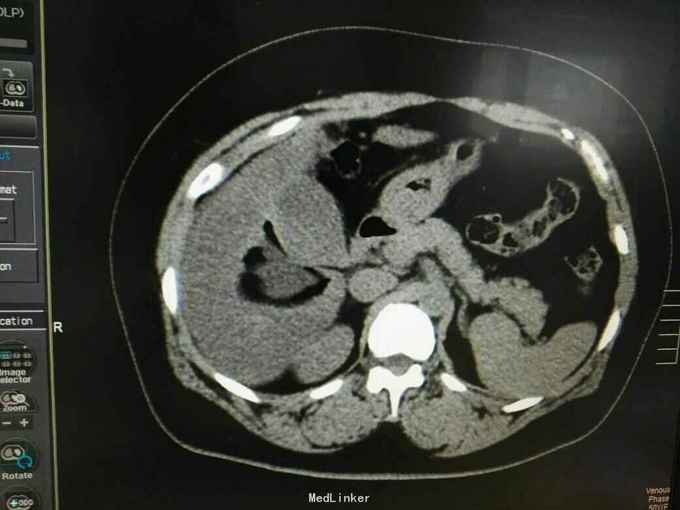

巨大肝囊肿

发现肝脏占位10年

肋弓下可触及囊性占位

肝囊肿

今日在局麻下行囊肿穿刺抽吸+无水酒精注射术 术中共抽取淡黄色液250ml